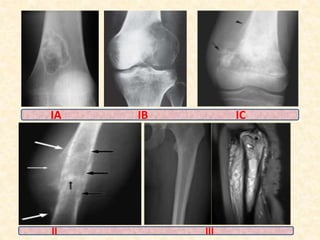

LODWICK’S IA well marginated without

deformation or expansion.

LODWICK’S IB well defined lesion, but

irregularly marginated .

Septated appearance.

Expansion, bulging or

deformation .

LODWICK’S IC ragged permeative interface

with adjacent bone

-Cortical

destruction,codmans triangle

etc

LODWICK’S II often have a generous

reactive rim of

cancellous bone

admixed with defects of

extra capsular &/or soft

tissue extension

LODWICK’s III poorly marginated

interface with a

diffuse permeative

border.

HIGH GRADE SARCOMA

IA IB IC